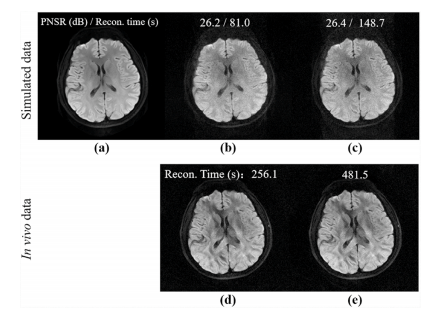

Fig. 16. Comparison of one-direction and two-direction DONATE with 8-shot simulated data (1st row) and in vivo data (2nd row). (a) is the noise-free ground truth. (b) and (d) are the results of one-direction DONATE, while © and (e) are the two-direction DONATE. PSNR and reconstruction time are marked at the top of the images. Note: The 1st row comes from a 8-channel simulated DWI data with noise (10 dB) as in (Qian et al., 2023b). The 2nd row comes from in vivo DATASET VI.

图16:使用8次激发的模拟数据(第一行)和体内数据(第二行)对单向DONATE和双向DONATE进行比较。(a) 是无噪声的真实数据。(b) 和 (d) 是单向DONATE的结果,而 © 和 (e) 是双向DONATE的结果。峰值信噪比(PSNR)和重建时间标注在图像的顶部。注意:第一行数据来自如(钱等人,2023b)所述的带有噪声(10分贝)的8通道模拟弥散加权成像(DWI)数据。第二行数据来自体内数据集VI。